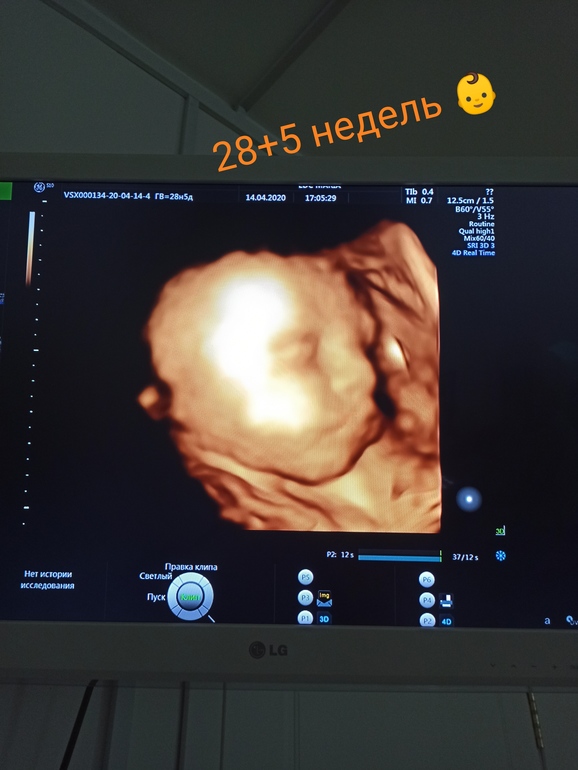

я делала дважды) не прлучалось, лежал плохо. а потом соучайно вдруг сделали фотку на 34-35 уже примерно неделе) по мне-интересно, но все равно непонятно же, как будет выглядеть

у меня на узи вон какой нос был)